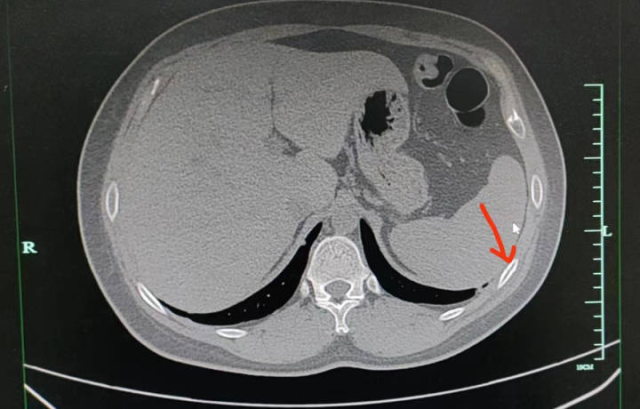

医生注意到,正常状态下,聂先生胸口只有轻微痛感,但在咳嗽或按压时,疼痛会明显加重。经过进一步的CT检查发现,聂先生右侧第五、第六肋骨都骨折了。

图片

医生解释,肋骨骨折与其他骨折不同,它不承受重量,所以在静息状态下通常没有疼痛感。但当肋骨受到外力按压或胸廓活动较大时,如咳嗽或深呼吸,就会引发疼痛。

“咳断肋骨的情况在骨质疏松的老年患者中较为常见。像聂先生这样年轻、体型正常、营养均衡的患者是较少见的案例,可能是由于咳嗽时间持续过久,造成了肋骨部位反复受到牵拉而引发的疲劳骨折。”医生表示。